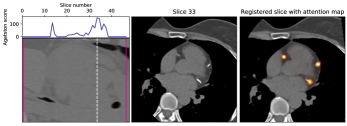

V-C Decision feedback

Decision feedback visualizes attention of the calcium scoring ConvNet. This feedback informs and end-user about the regions that contributed to the calcium score. Figure 7 shows examples of such feedback. The feedback helps an expert to quickly navigate and evaluate the image slices containing CAC.

We propose visual feedback as an optional qualitative tool, but we have performed a quantitative analysis to provide insight in its accuracy. To obtain quantitative results we analyzed heatmaps for slices with predicted calcium scores. The heatmaps were warped to the original image spaces by using the inverse transformation matrices. The values of the heatmaps were scaled between 0 and 1 to mimic probability maps for CAC candidate voxels. CAC candidates were defined as high density 26-connected voxels with a volume between 1.5 and 1,500 mm3[19]. For evaluation of these maps we performed precision-recall analysis (Figure 8). We have defined an optimal threshold by selecting the maximum F1 (i.e. Dice) score on the validation set. Table IV shows the obtained scores using the selected threshold on the test sets. The results show that detection performance is very accurate on the validation set as well as the test set.

Additionally, decision feedback aided our analysis by clarifying incorrect calcium scores. Decision feedback revealed that the largest CVD miscategorizations were not caused by incorrect quantification but by incorrect recognition of CAC. Figure 9 shows six examples of the largest miscategorizations made by the calcium scoring ConvNet. The majority of errors were made in identification of calcifications near the coronary artery ostia. Calcifications near the ostia can be partly in the aorta and partly in the coronary artery. These calcifications are difficult to distinguish, especially when no information of neighboring slices is available.